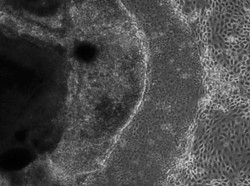

iPSから目の主要細胞 - 大阪大が作製、世界初

人の人工多能性幹細胞(iPS細胞)から、角膜の一部や水晶体、網膜など目の主要な部位の細胞をまとめて作ることに大阪大の西田幸二教授(眼科学)のチームが世界で初めて成功し、9日付英科学誌ネイチャー電子版に発表した。 目のレンズに当たる角膜部分をウサギに移植 ...マイナビニュース ·